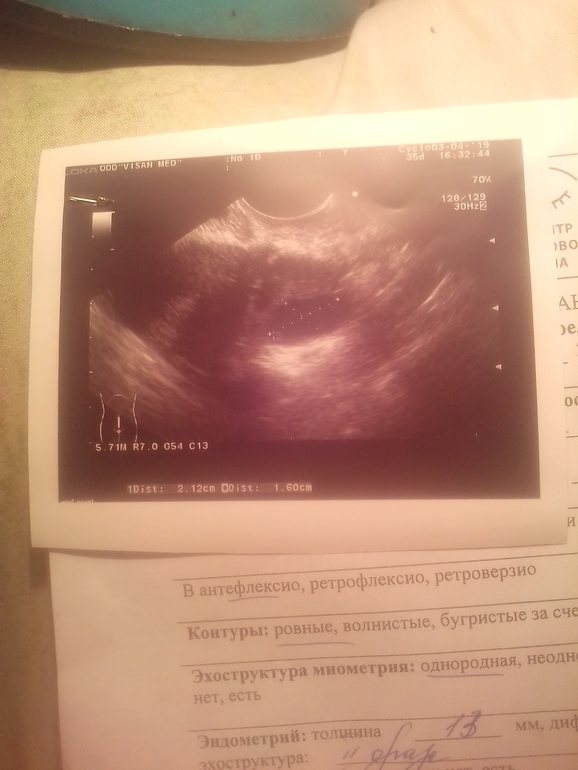

Очень нечеткая фотка, непонятно. Если края ровные, содержимое черное - фолликулярная. То, что чувствовали, - это напряжение, с которым фолик пытался лопнуть, т.е мог не лопнуть. И яичник тянет по этой же причине - либо "разбухает", либо ЖТ, ощущения похожи, так что на них не стоит опираться.

У вас на снимке прямо по центру черный круг, на нём стоит метка измерения от края до края - узист замеряла его размеры. Вот это оно и есть, про что вы спрашиваете

а ещё, я где-то читала, что у ЖТ кисты или обычного - есть кровоток по краям, А фолликула нет. Но тут не ясно - делала ли узистка Допплер или не делала.